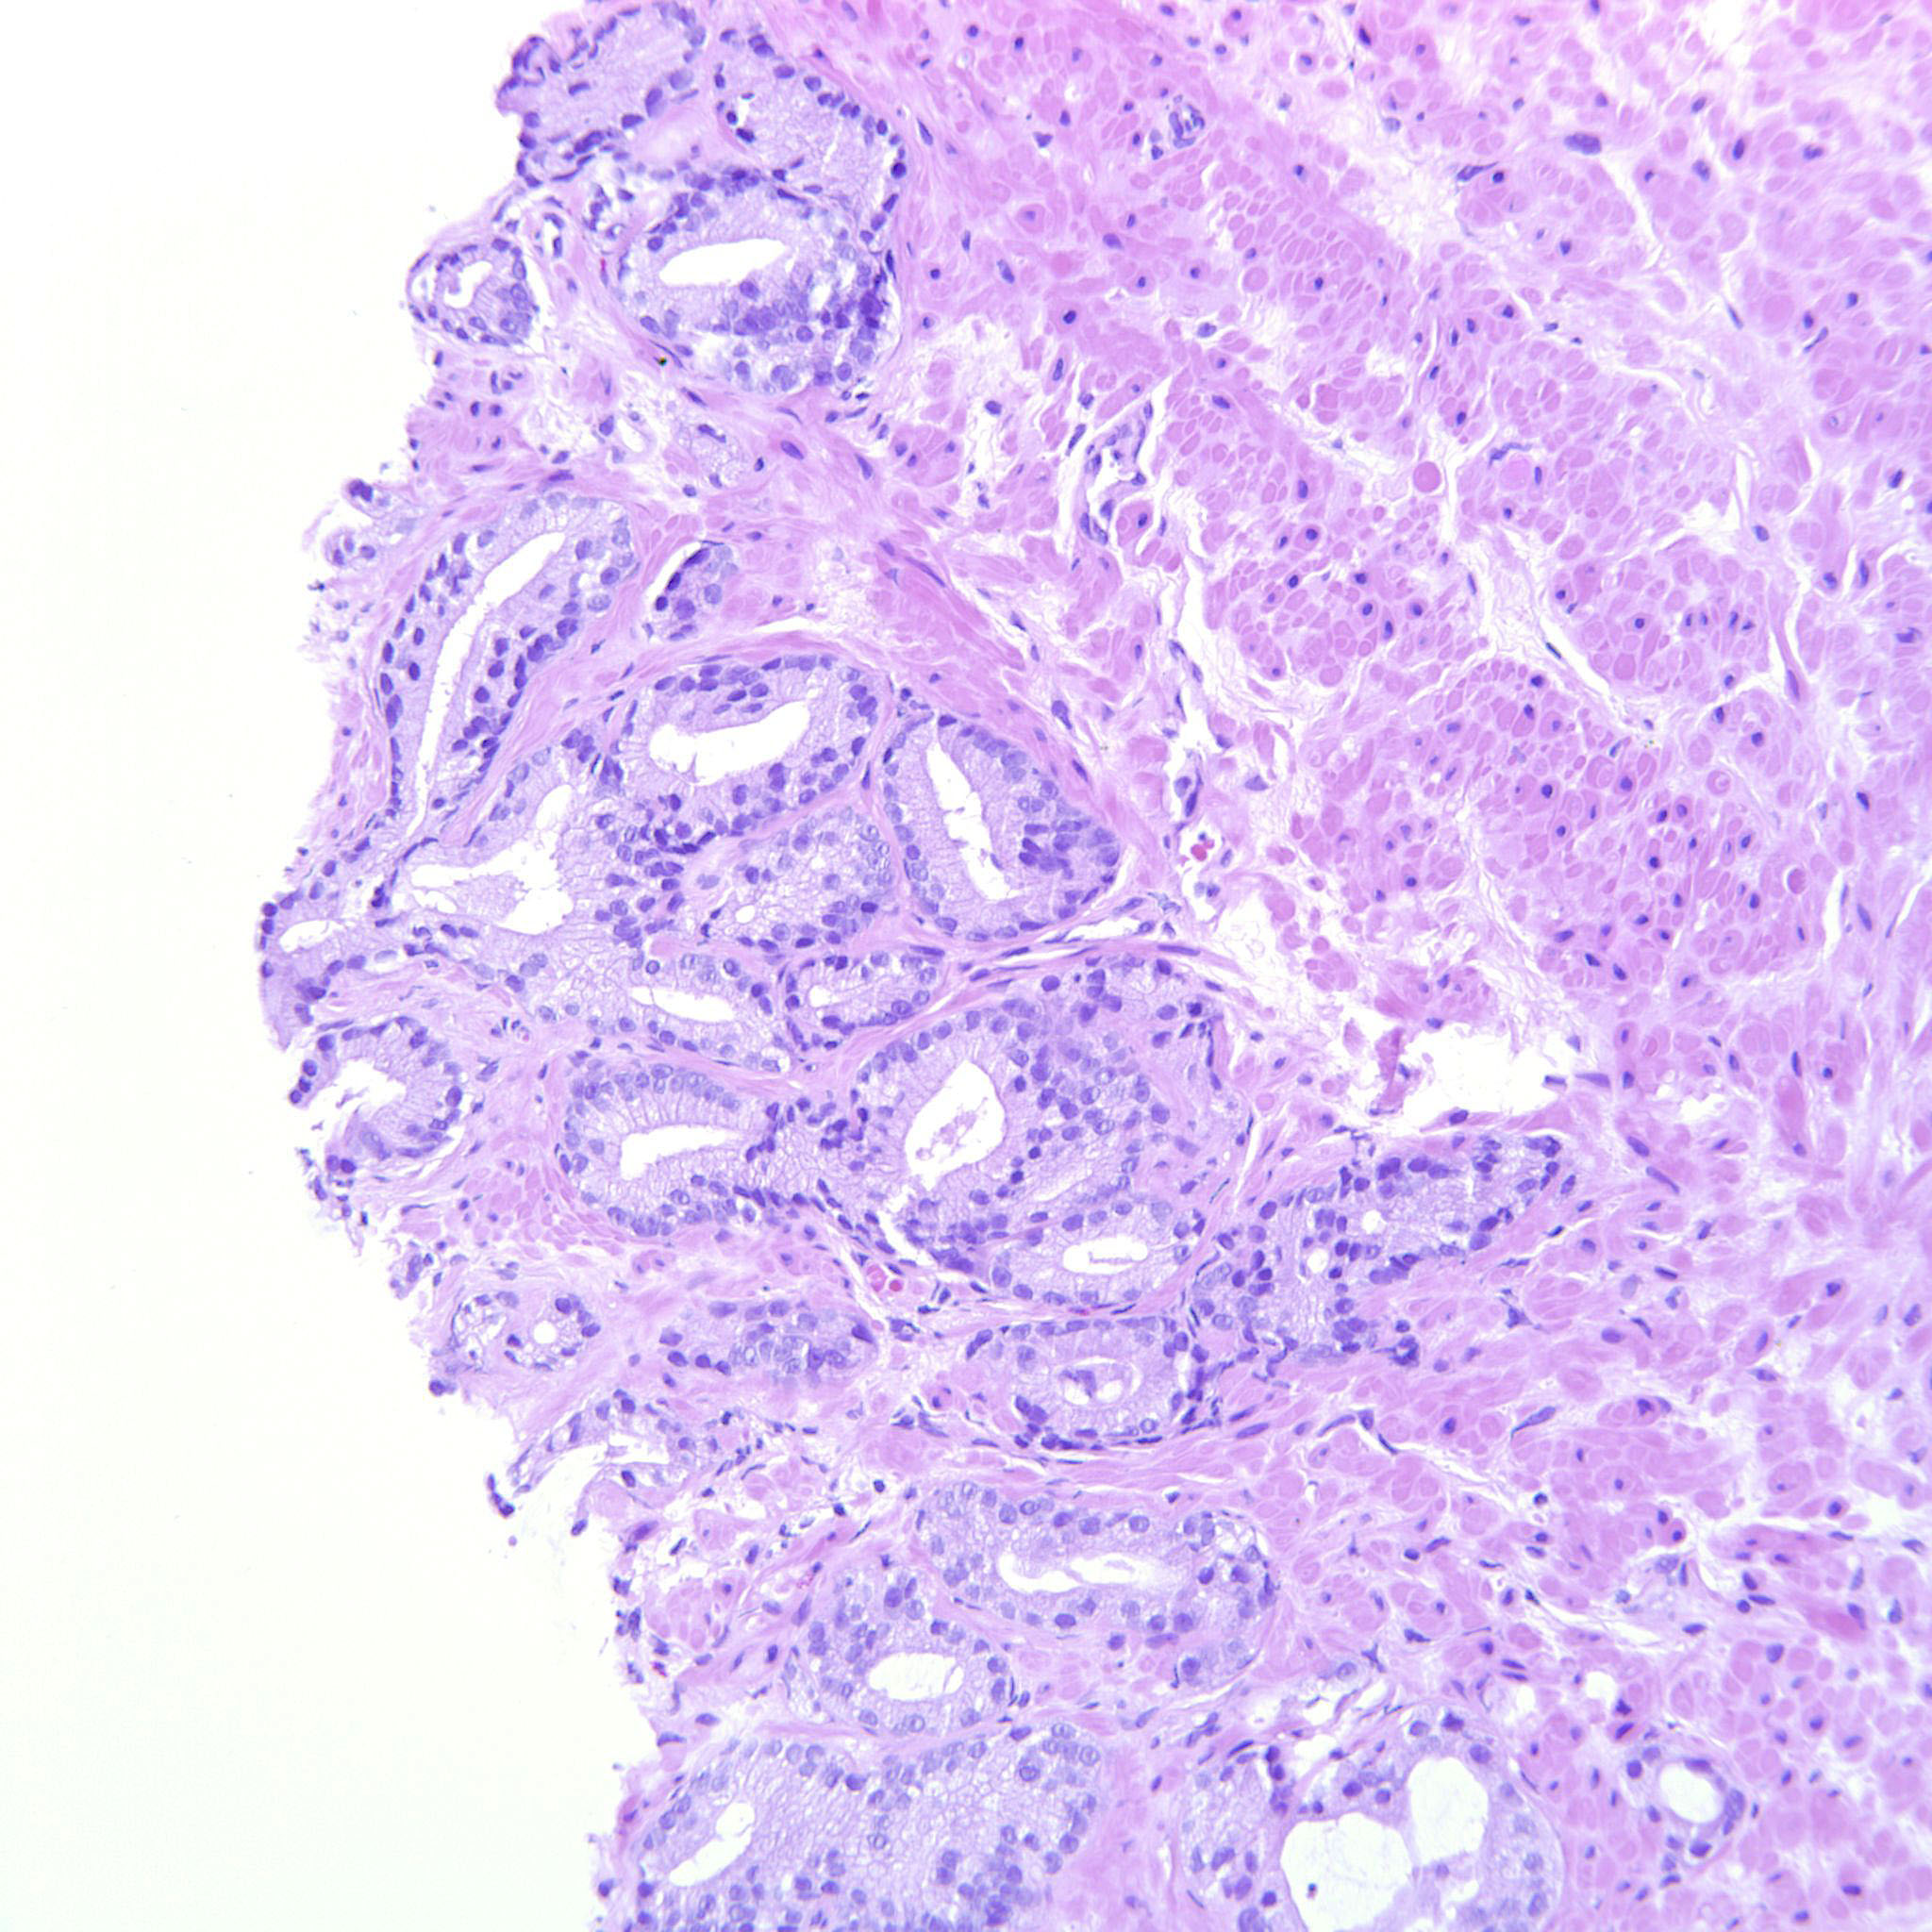

Prostate cancer grading

Case ID: 704